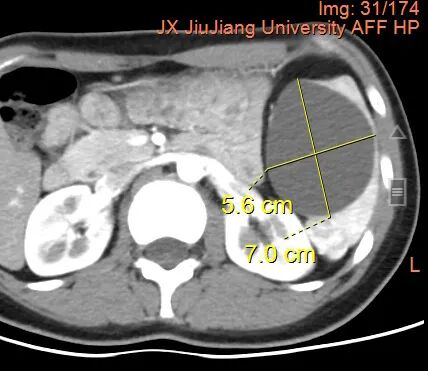

肿瘤占位

因脾脏质地脆弱且血供丰富,手术过程中稍有不慎便可能引发大出血,甚至危及患者生命。此外,脾脏位于左上腹,周围毗邻胃、胰腺、右肾、结肠等多个重要脏器,对术者的技术、耐心和经验要求极高。为确保手术成功,大外科主任方宏才、肝胆外科副主任余涛等制定了严密的手术计划,利用影像学检查精准定位肿瘤范围和血管走向,精细解剖脾门血管,运用超声刀、精准缝合等先进技术,成功切除肿瘤并保留了超过30%的健康脾脏,术中出血量极小。